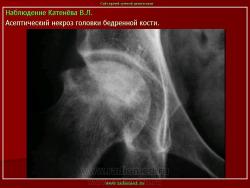

Остеохондропатия головки бедренной кости

(болезнь Легга-Кальве-Пертеса)

Изменения на рентгенограммах зависят от стадии процесса.

В I стадии (асептиче­ского некроза губчатой кости эпифиза и костного мозга) изменения отсутствуют либо незначительные: в виде остеопороза костей, образующих тазобедренный сустав, извилистости и неравномерности хрящевой эпифизарной пластинки, неоднородности и пятнистости шейки бедра, некоторого расширения щели сустава.

Во II стадии (импрессионного перелома) головка бедренной кости утрачивает характерную трабекулярную структуру, шейка бедра становится более остеопоротичной. Суставная щель отчетливо расширяется по сравнению со здоровым тазобедренным суставом. Эпифиз головки уплотняется, склерозируется и деформируется (вследствие сохраняющейся нагрузки).